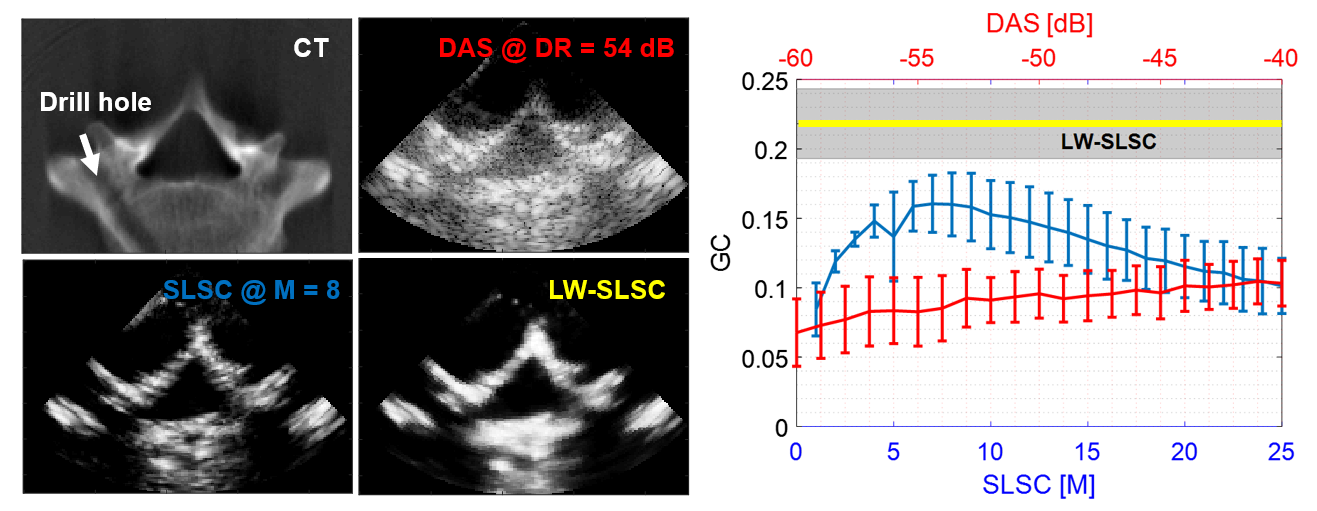

Instead of averaging the cumulative sum up to a lag value M (out of a preselected total of N lags, where M≤N), LW-SLSC beamforming computes the weighted coefficients for N lags by minimizing the total variation of the weighted sum within a moving kernel. In order to preserve the high resolution located at higher lags, this adaptive solution is regularized using the L2-norm with a gradient operator. US channel data was acquired for 10 different views of a human vertebra submerged in deionized water using an Alpinion ECUBE-12R system and SP1-5 phased array probe (3.8 MHz center frequency, 65 mm depth, 50 mm focus). SLSC images were computed with M varying from 1 to 25, and DAS images were created with the dynamic range (DR) varying from -60 to -40 dB. LW-SLSC images were computed with a 1.20 mm (lateral) x 1.92 mm (axial) kernel, N=50, 50% overlap and 0.1 regularized coefficient obtained from L-curve tests. The Gradient Correlation (GC) was measured to evaluate the bone structure similarity of each ultrasound imaging method when compared to CT images.

Example CT, DAS, SLSC and LW-SLSC images are shown in Fig. 1 alongside the mean standard deviation of GC measurements. Overall, SLSC outperforms DAS for a range of parameters commonly used in the literature (e.g., M=5-25, DR=-50 to -60 dB) when considering the similarity of bone structures in the CT and US-based images. An additional improvement is observed with LW-SLSC over SLSC (e.g., 8.2 dB mean contrast-to-noise ratio increase, 0.10 mean GC increase)